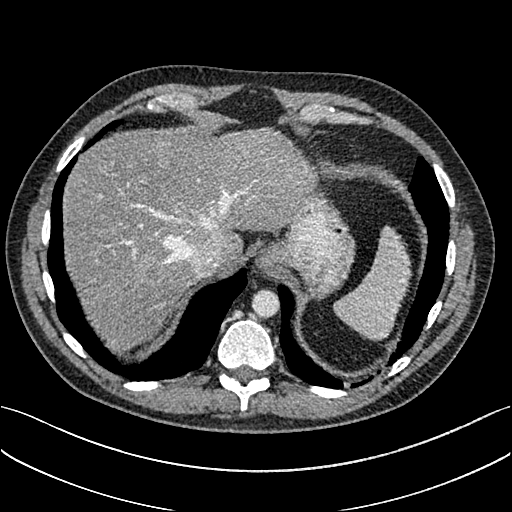

To demonstrate the effectiveness of the proposed network, we perform the qualitative comparisons over three representative abdominal images presented in Figs. 3, 5 and 7. For better evaluations of the image quality with different denoising models, zoomed regions-of-interest (ROIs) are marked by red rectangles and shown in Figs. 4, 6 and 8 respectively. Note that all results from different denoising models focus on two aspects: content restoration and noise-reduction. All CT images in axial view are displayed in the angiography window [-160, 240]HU.

The real NDCT images and corresponding LDCT images are presented in Figs. 3a and 3b. As observed, there are distinctions between ground truth (NDCT) images and LDCT images. Figs. 3a and 7a show the lesions/metastasis. Fig. 5a presents focal fatty sparing/focal fat. In Figs. 4a, 6a and 8a, these lesions can be clearly observed in NDCT images; in contrast, from Figs. 4b, 6b, and 8b, it can be seen that the original LDCT image is noisy, and lacks structural features for task-based clinical diagnosis. All adopted denoising models suppress noise to some extent.

From Figs. 7 and 8, we can see mean-based and SL-based methods work well with effective noise suppression and artifact removal. However, the illustrations in Fig. 8 show that these methods blur the local strutural features. Our proposed SMGAN-based methods present a better edge preservation than the competing methods.